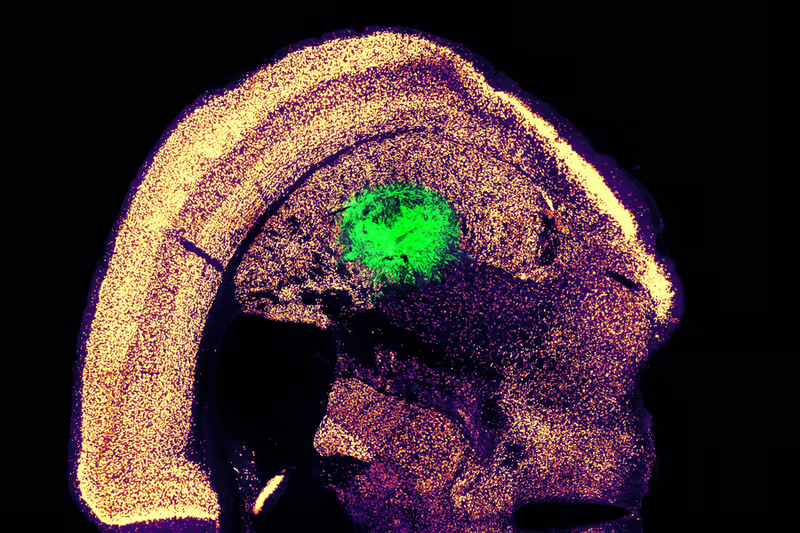

محققان این روش را با تبدیل سلول‌های پوست موش به نورون‌های حرکتی آزمایش کردند و شاهد بازدهی بیش از ۱۰۰۰ درصدی بودند. نورون‌های حرکتی به دست آمده، فعالیت الکتریکی قابل تشخیص و سیگنال‌های کلسیمی داشتند که نشان‌دهنده عملکرد آنهاست. در آزمایش‌های بعدی، نورون‌ها به مغز موش‌های زنده پیوند زده شدند که در آن جا با سلول‌های دیگر مغز ارتباط برقرار کردند.

نسخه‌ای از این روش برای سلول‌های انسانی نیز توسعه داده شد، اگرچه در این مرحله راندمان کمتر چشمگیر بود و بین ۱۰ تا ۳۰ درصد مشاهده شد. با این حال، این شروع بهتری است و محققان قصد دارند به کار برای افزایش این کارایی ادامه دهد.